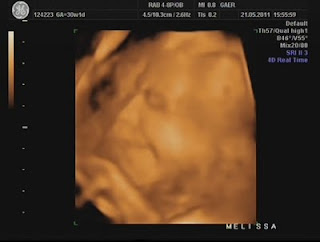

Hoje foi dia de análises e eco...

Durante a eco, percebi que a Dra ficou tempo a mais a avaliar o mesmo local e ao fim ela me explicou que viu uma lamina de água a volta do coraçãozinho da minha pricesa.

Ela me explicou que isso acontece a alguns bebés e que não devo me preocupar, que temos que fazer um exame mais detalhado para avaliar o coraçãozinho dela que será feito no Hospital São João e que hoje já trataria de marcar isso...